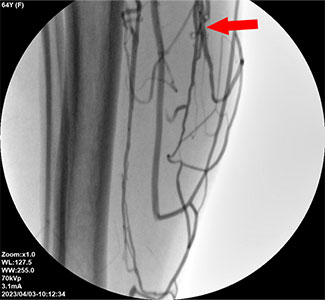

하지정맥류가 재발된 원인은 잔가지 혈관까지 살펴 바짝막지 못함하지정맥류 재발된 이유는 분명하기에 재발 원인부터 제대로 구분해야 합니다. 하지정맥류가 재발된 이유는 크게 2가지로 나뉩니다.

문제가 없었던 새로운 정맥에 이상이 생긴 경우와 이전에 치료한 혈관에서 증상이 재발한 경우입니다.

특히 치료한 혈관에서 다시 문제가 발생한 경우는 문제 혈관을 바짝 막지 못해 역류길이 새어 발생했다고 봅니다.

뿐만 아니라 문제 혈관 주위로 잔가지 혈관에서 미세하게 발생한 역류를 미처 발견하지 못하고 놓친 경우도 포함됩니다.

결과적으로 잔가지 혈관까지 살펴 혈관을 바짝막지 못한 것이 재발한 주요 원인이라 할 수 있습니다.